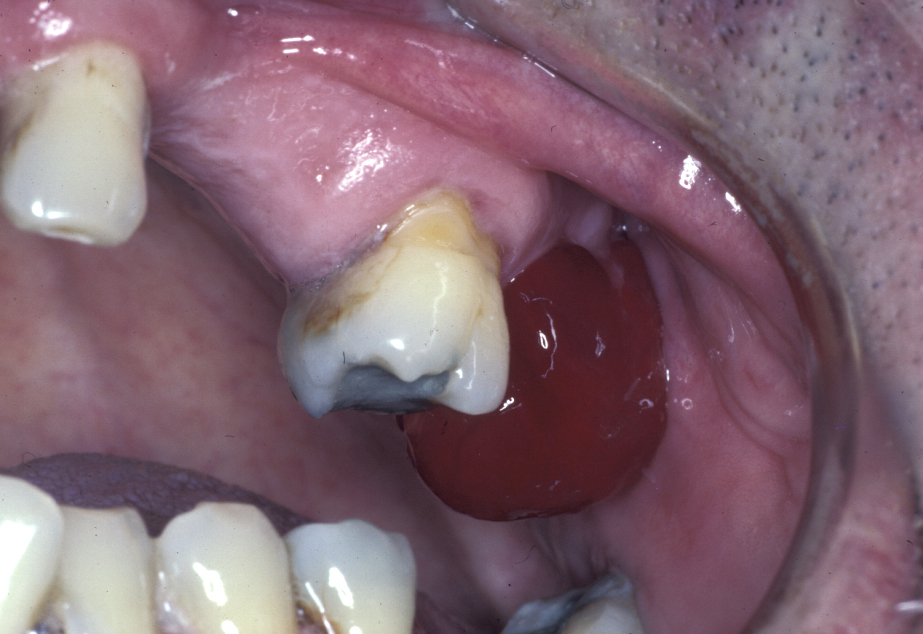

An oroantral fistula (a communication between the oral cavity and the maxillary sinus (antrum) is a common condition. Lining of the antrum may prolapse through such a fistula (Figure 1), or the fistula will have become lined with epithelium (thin, surface-covering tissue) as shown in Figure 2.

Figure 1: Clinical view of antral lining prolapsing through an oroantral communication.